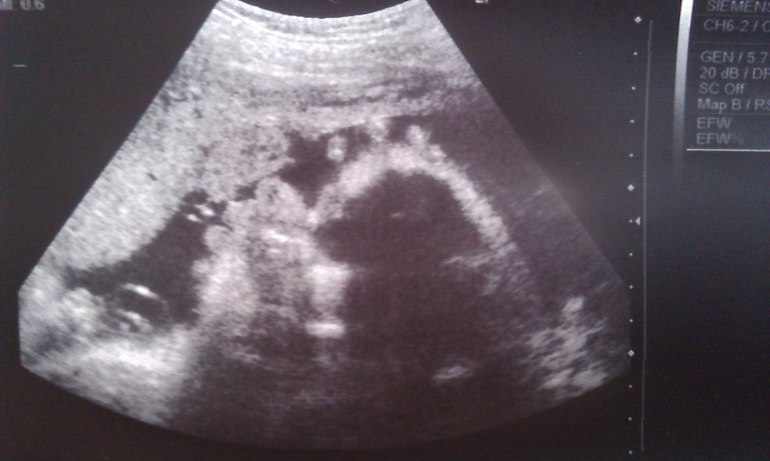

Со звонком в 30 недель, тут же получила от врача кучу направлений на анализы, походы по врачам. 2-й плановый осмотр, ну и конечно записалась на долгожданное УЗИ)

31.07 Записалась на УЗИ с доплером, а то меня напугали, что в такую жару, часто кислородное голодание, ребенок не до получает кислород, развивается гипоксия и все в таком духе.

Как только я увидела "малышку" на экране, я аж приподнялась. Она такая большая, мне показалось, что там уже ребенок огромный))) Но успокоили, сказали, что все хорошо. Идем как и всегда с опережение по сроку, теперь уже в 2 недели, вместо 1,5. Доча крутилась, вертелась, пару раз сладко зевнула. Показывая личико я поняла одно, моего там нет НИ-ЧЕ-ГО! Папина копия) Чему я была очень рада))

Рост наш аппарат насчитал 51см

, а вес 2100кг

После озвучки таких цифр, я была в шоке. Я все понимаю, мы с мужем не крошки, но размеры меня пугают. Врач сказала. что родимся мы около 3700-3800кг. И это с моими планами на 3000-3100... Маааамооочкаа)))

Обвитий нет, доплер хороший, плацента 1-й степени зрелости. Ну это главное.

P.S. Принесла мужу фоточки с УЗИ. Крутил, вертел, и выдает: А че у нее мозг черный? И че, за гребень?)) И что она там ест?))

Смеялась до слез))) Пока я объяснила что это не гребень, а всего лишь пальчики попали в кадр над головой)) И мозг у ребенка не черный, а такой получился ракурс)) И ничего она не ест)) Думала поседею))